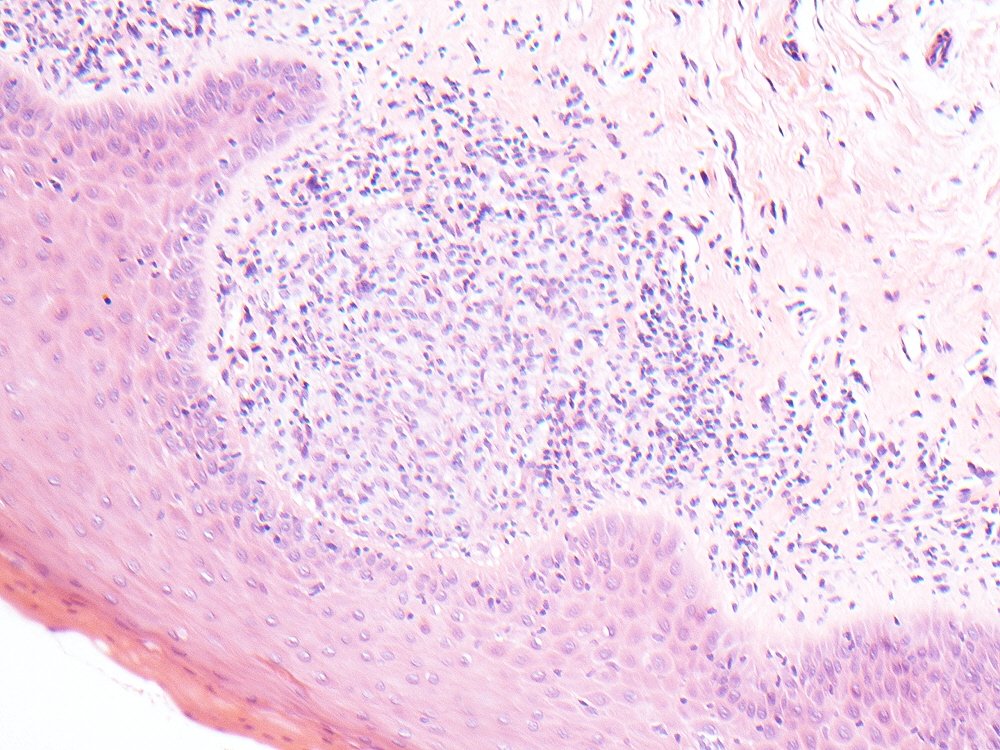

Biopsy of lichen planus of the lateral tongue which shows a submucosal aggregate of foamy macrophages #oralpath #pathology